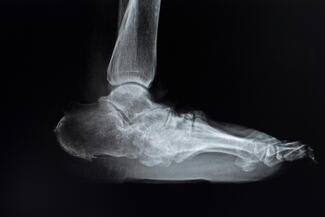

In this video, Dr. Abicht dives into key components of radiographic assessments.